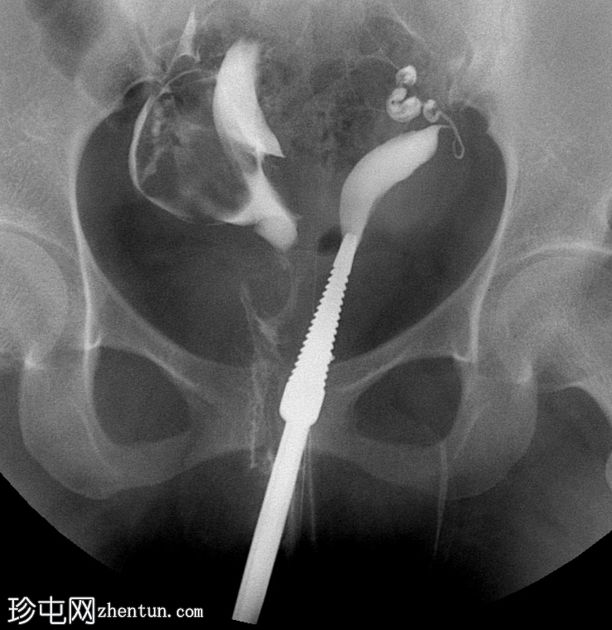

子宫输卵管造影

正位

子宫输卵管造影显示两个独立的子宫腔,完全重复。可见两条独立的宫颈管。每个子宫角分别与其对应的输卵管相通。无统一的子宫底;子宫角明显分离。两个子宫腔均充盈并溢入腹腔。

子宫输卵管造影 (HSG) 显示两个间距较大的子宫腔和两个宫颈,强烈提示双子宫。

仅凭 HSG 可能不足以确诊——通常需要进一步影像学检查(MRI/三维超声)来评估子宫外轮廓并排除其他苗勒氏管畸形。